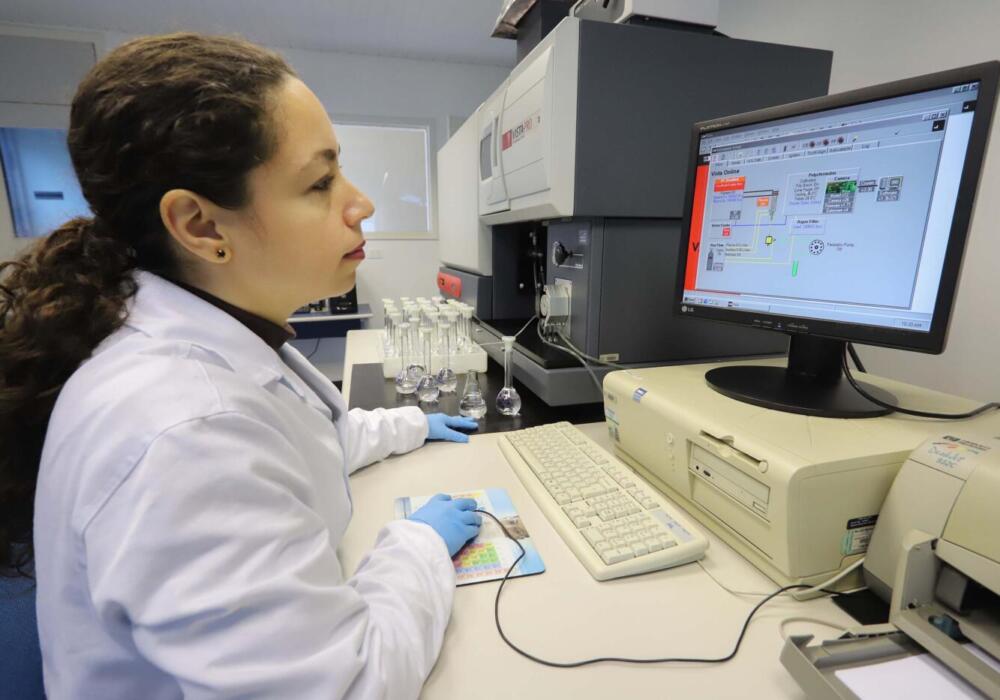

Das 82 publicações científicas divulgadas de janeiro a junho de 2022, 43 foram enviadas por pesquisadores de países da Ásia, África e América do Sul. A...